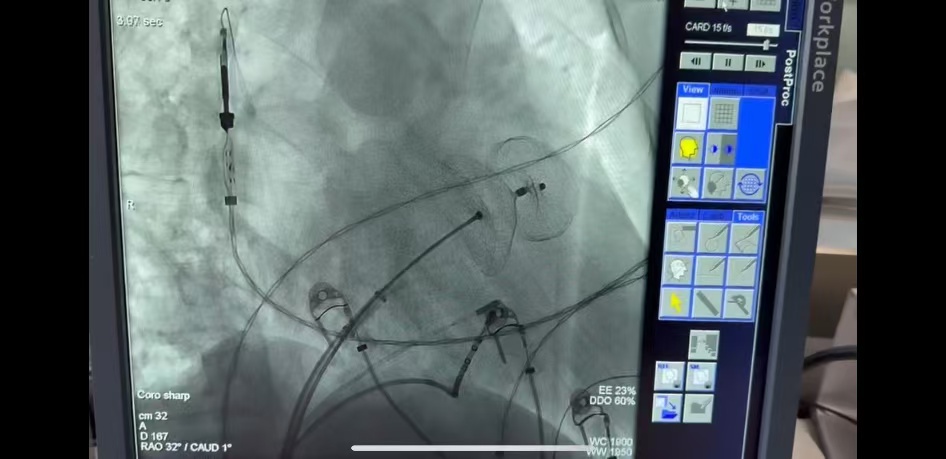

手术当日,心内科亢主任团队在安贞医院傅彪教授指导下,手术流程一气呵成。局麻下首先使用三维线性脉冲压力导管在三维电生理导航系统指导下快速、精准地完成了肺静脉电隔离、心房碎裂电位消融、二尖瓣峡部线消融,消融过程中房颤转房扑,消融二峡时心脏恢复规整节律。随后,左心耳造影,选择LAAO-I 3440左心耳封堵器,多角度观察封堵位置满意,心耳口部无残余分流,牵拉试验无异常。